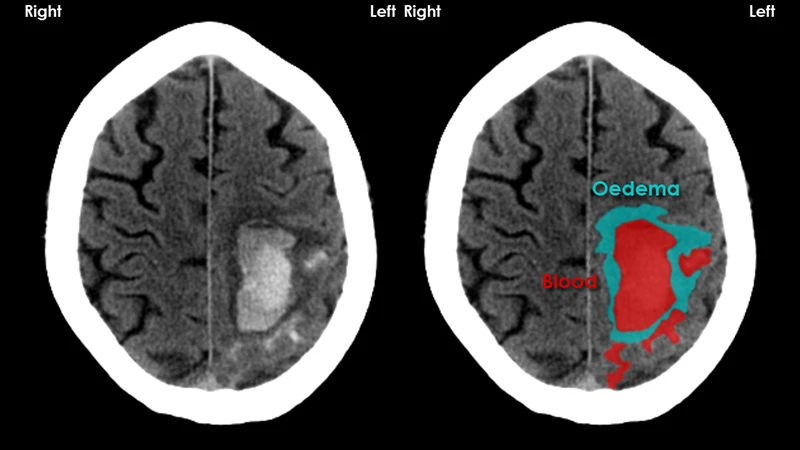

- Stroke: A non-contrast head CT is the primary tool for diagnosing a stroke. It can instantly determine if the stroke is caused by a bleed (hemorrhagic) or a clot (ischemic), which require completely different treatments.